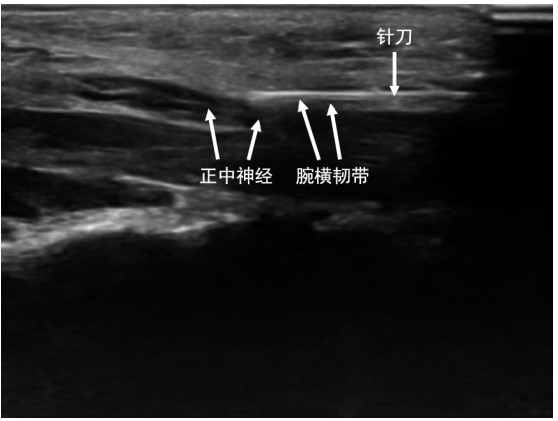

补肾活血汤联合单侧双通道脊柱内镜治疗肾虚血瘀型腰椎管狭窄症的临床研究

鄂远, 黄盛昌, 芮立宁

2025, 23(10): 1764-1767. doi: 10.16766/j.cnki.issn.1674-4152.004224

1 0

摘要:

目的  观察补肾活血汤联合单侧双通道脊柱内镜(UBE)对肾虚血瘀型腰椎管狭窄症(LSS)患者的恢复情况、机体炎症、术后并发症的影响,探究中西医联合治疗对肾虚血瘀型LSS患者的疗效及作用机制。  方法  选取2023年6月—2024年4月常州市武进中医医院符合纳排标准的120例肾虚血瘀型LSS患者,按随机数字表法分为治疗组(给予补肾活血汤联合UBE治疗)和对照组(UBE治疗)。比较2组视觉疼痛模拟评分法(VAS)评分、Oswestry功能障碍指数(ODI)评分、血清干扰素γ(IFN-γ)/白细胞介素-1α(IL-1α)等指标。  结果  治疗总有效率比较,观察组高于对照组[86.67%(52/60) vs. 71.67%(43/60),χ2=4.093, P=0.043]。术后2周、术后1个月,观察组的VAS评分低于对照组(P<0.05)。术后1、6个月ODI评分比较,观察组低于对照组(P<0.05)。治疗后,观察组外周血血清IFN-γ、IL-1α均低于对照组(P<0.05)。观察组术后并发症总发生率低于对照组[6.67%(4/60) vs. 23.33%(14/60),χ2=6.536,P=0.011]。  结论  补肾活血汤联合UBE可显著提高肾虚血瘀型LSS治疗效果,降低肾虚血瘀型LSS患者术后VAS、ODI评分,降低血清IFN-γ、IL-1α浓度,且可降低术后并发症发生风险。